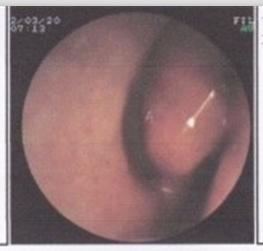

【鼻甲肥大该怎么护理】很多人不清楚什么是鼻甲肥大?贵阳耳鼻喉医院专家表示:其实在人体的鼻腔中,共有三对鼻甲,其中以下鼻甲排名靠前、最长,而且最靠近鼻孔,更容易受到各种外界刺激,而产生炎症反应,引起鼻甲粘膜充血而水肿,堵塞鼻腔,形成鼻甲肥大。